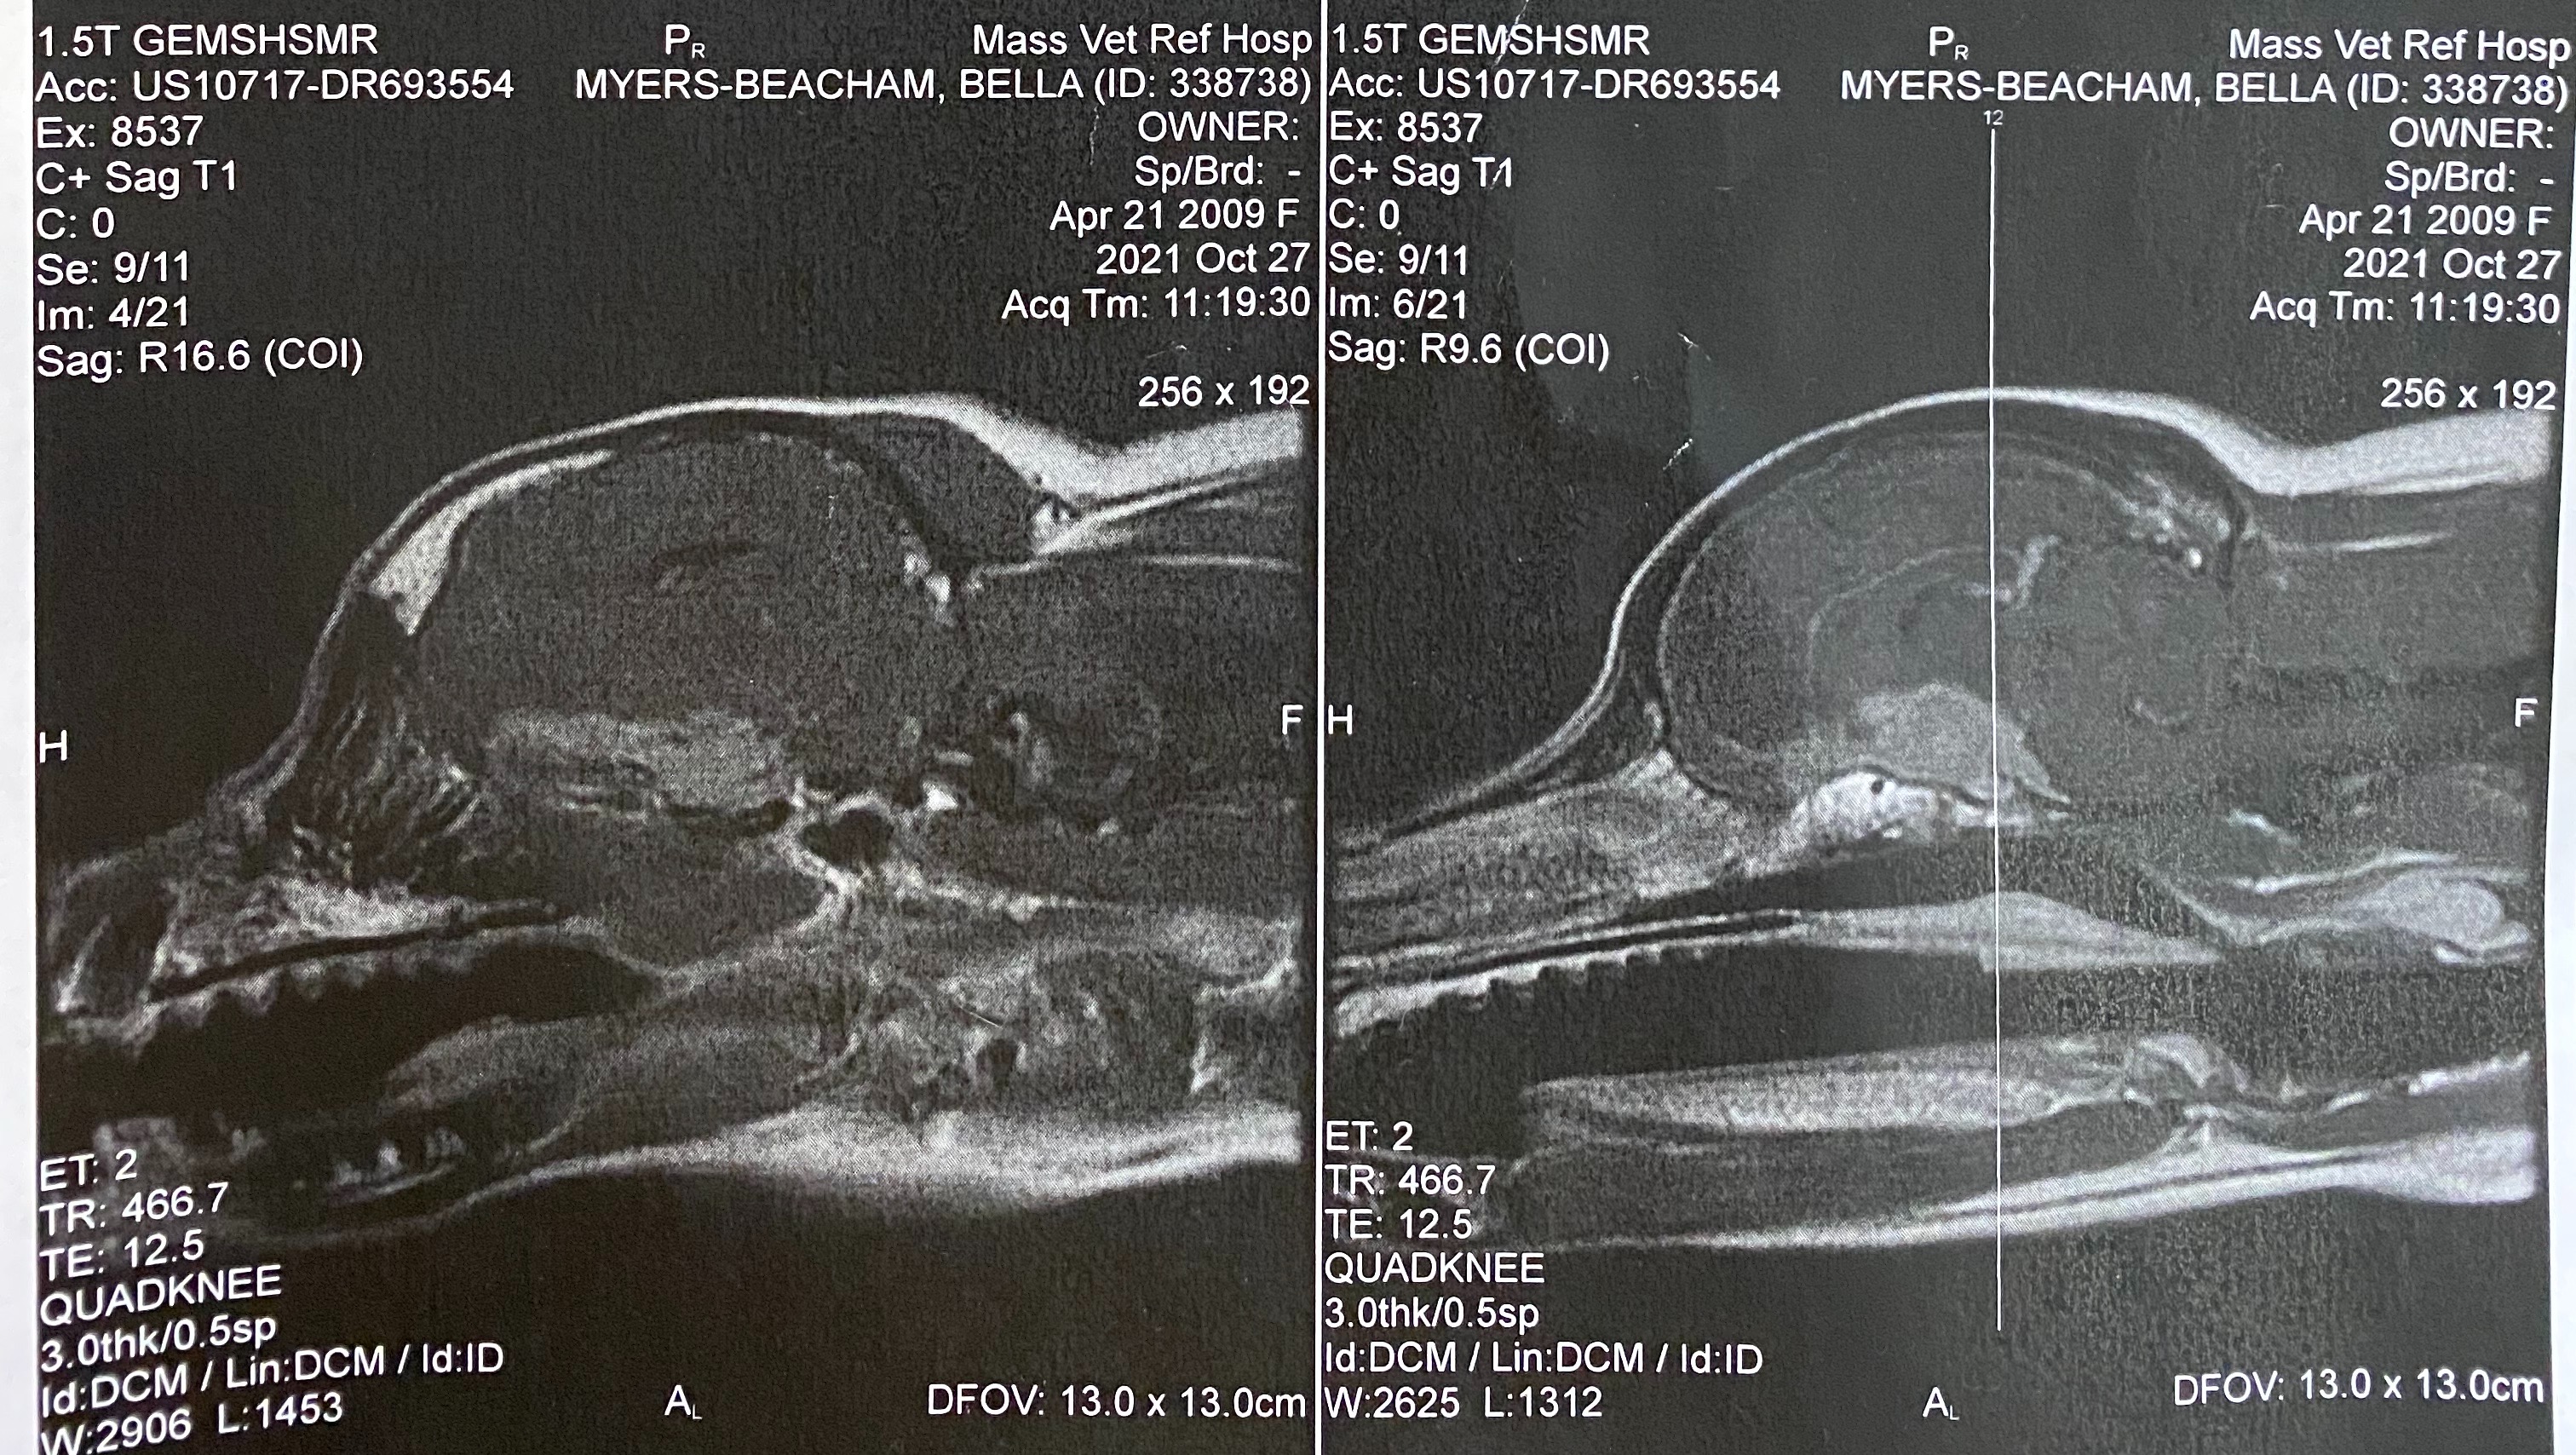

Bella had her MRI on 10/27/2021. Imaging revealed a large, broad based, extra-parenchymal mass located ventral to the brain from the frontal lobes to the cranial mesencephalon. The mass is compressing her optic nerves, explaining the blindness. Based on the location of the mass, we are told surgery is not a viable option.